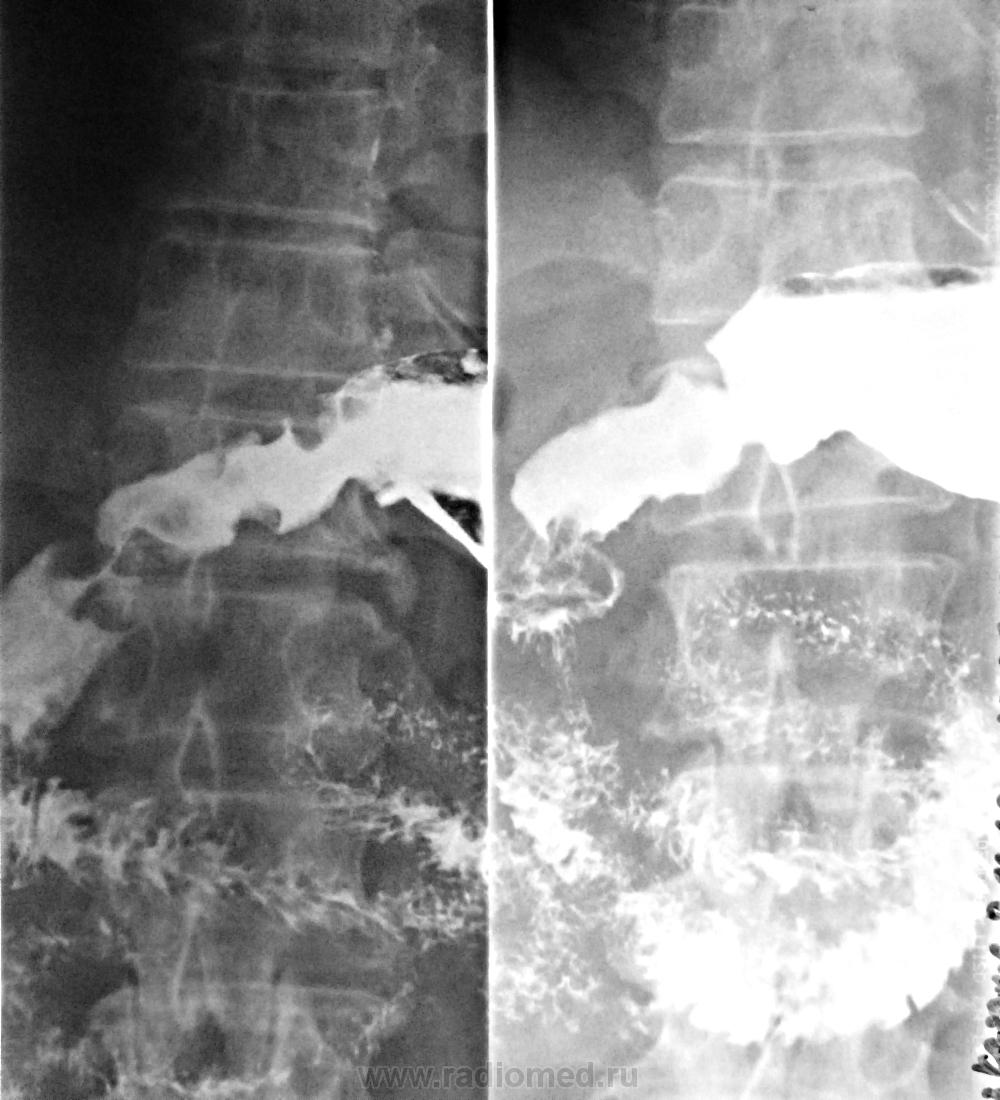

Пациент без активных жалоб. Обследуется впервые с панкреатитом. РС желудка выполнена через 2 суток после ФЭГДС. КлАК спокоен.

Рак антрального отдела, смешаная форма роста.

Может, полипы? Контуры для рака какие-то уж больно четкие.

Коллега, brainmodel,  не представлено ни одного снимка дистальных отделов желудка, в условиях двойного контрастирования- как я понял, вы не пользуетесь этой методикой?

Нет. Только нативно - сколько воздуха заглотит. Кстати, заглотил он хорошо, свод и тело раздулись как шар, а в антрум не пошло. На ФЭГДС - поперечно гипертрофированные, гладкие, ограниченно эластичные складки в антруме, деформирующие и сужающие его просвет, с плохой расправляемостью просвета, без эрозирования, без имбибиции индигокармина (может и эндофитный рак). На скопии перистальтика, хоть и поздняя, но сохранена. Фарм пробы не делались. Поставил "ригидный антральный" до прибытия гистологии (2-3 нед), а там посмотрим еще раз.